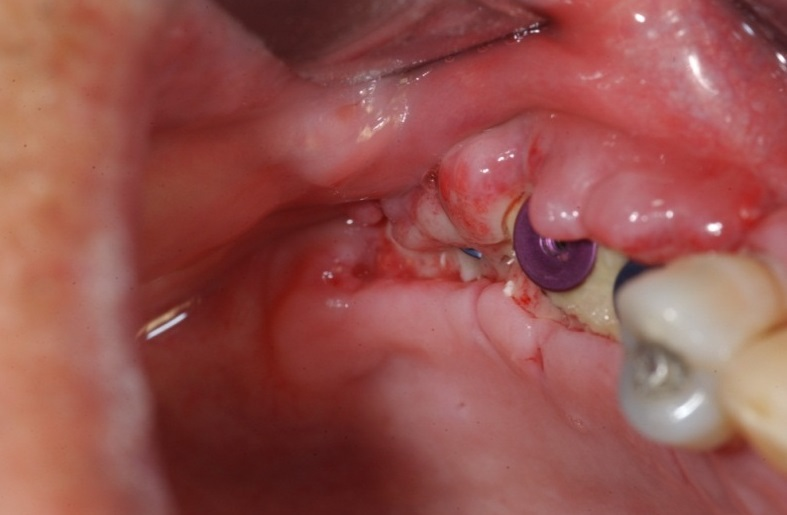

Trụ Implant bị rơi vào trong xoang hàm

Trong quá trình thăm khám, nếu bác sĩ không chẩn đoán đúng hoặc thiếu kiến thức về giải phẫu, chẩn đoán hình ảnh thì sẽ không thể phát hiện được đáy xoang. Do đó khi khoan sẽ làm thủng đáy xoang, gây tổn thương và viêm xoang mãn tính.

Một trong những triệu chứng của viêm xoang đó là đau dai dẳng, đau nửa đầu hoặc đau dưới hốc mắt quá 7 ngày không hết sau khi cấy ghép Implant. Mức độ nặng hơn có thể xuất hiện mủ hoặc chảy máu từ mũi xuống họng sau phẫu thuật.